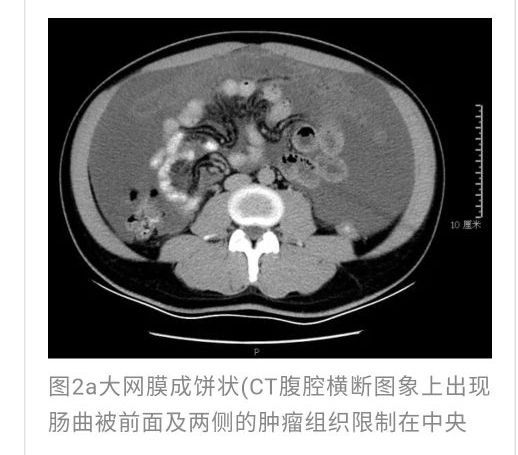

全腹CT:(1)结合病史考虑腹膜炎(见图2A),大量腹水;(2)右骼窝区管状样结构,考虑阑尾扩张(见图2B);(3)肝脏多发小囊肿(见图2C);(4)肝内胆管轻度扩张,建议隔期复查。

本例确诊后对B超及CT再次回顾发现:腹腔、盆腔可见不均质中强回声包块,部分呈囊实状,腹膜增厚,大网膜成饼状(如图2A)和肝周可见不均质中强回声弧形压迹、脾周可见不均质中强回声包饶,肝脏成扇贝样改变(如图2C),但在诊断报告中未提及。有学者发现mantle和scalloping(如图2A,2C)在PMP中具有代表性,且mantle较scalloping更为常见,若mantel征同时伴有大小不一的囊性改变,则更具诊断价值。

与此同时,还应与肝硬化腹水、妇科肿瘤、肠梗阻等疾病相鉴别。此患者为男性,全腹CT及PET-CT均提示阑尾扩张,很大可能来源于阑尾黏液性肿瘤。阑尾黏性肿瘤早期可无任何症状,随着瘤体堵塞阑尾,累及浆膜下层,播散至腹盆腔,可形成大量的黏液性腹水,又称“胶腹”,则可出现腹痛、腹胀、腹围增加等症状。通过本病例分析认为此类患者,腹穿时若发现腹水不易抽出或抽出物为黏稠胶冻样,腹部B超提示液性暗区内有漂浮的团状回声有分隔,撞击腹部后可出现“礼花”样改变,肝脾包膜完整不光滑,有弧形压迹,全腹部CT示弥散占位,可见mantle和scallping征、大网膜成饼状且阑尾扩张应高度怀疑本病。